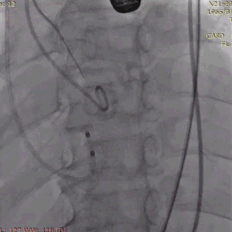

植入前冠脉造影

主动脉根部造影

直头导丝跨瓣

20mm球囊预扩

冠脉保护支架植入

AV23瓣膜释放到工作位

瓣膜完全释放

冠脉支架释放

植入后造影